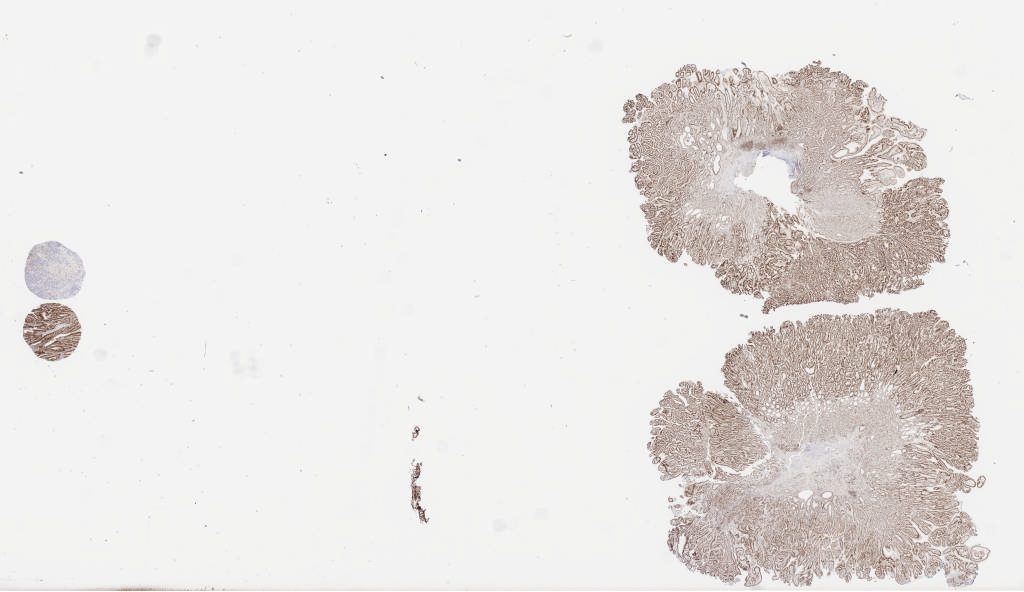

mlh 1a.svs

117528

x

67916

@

40X